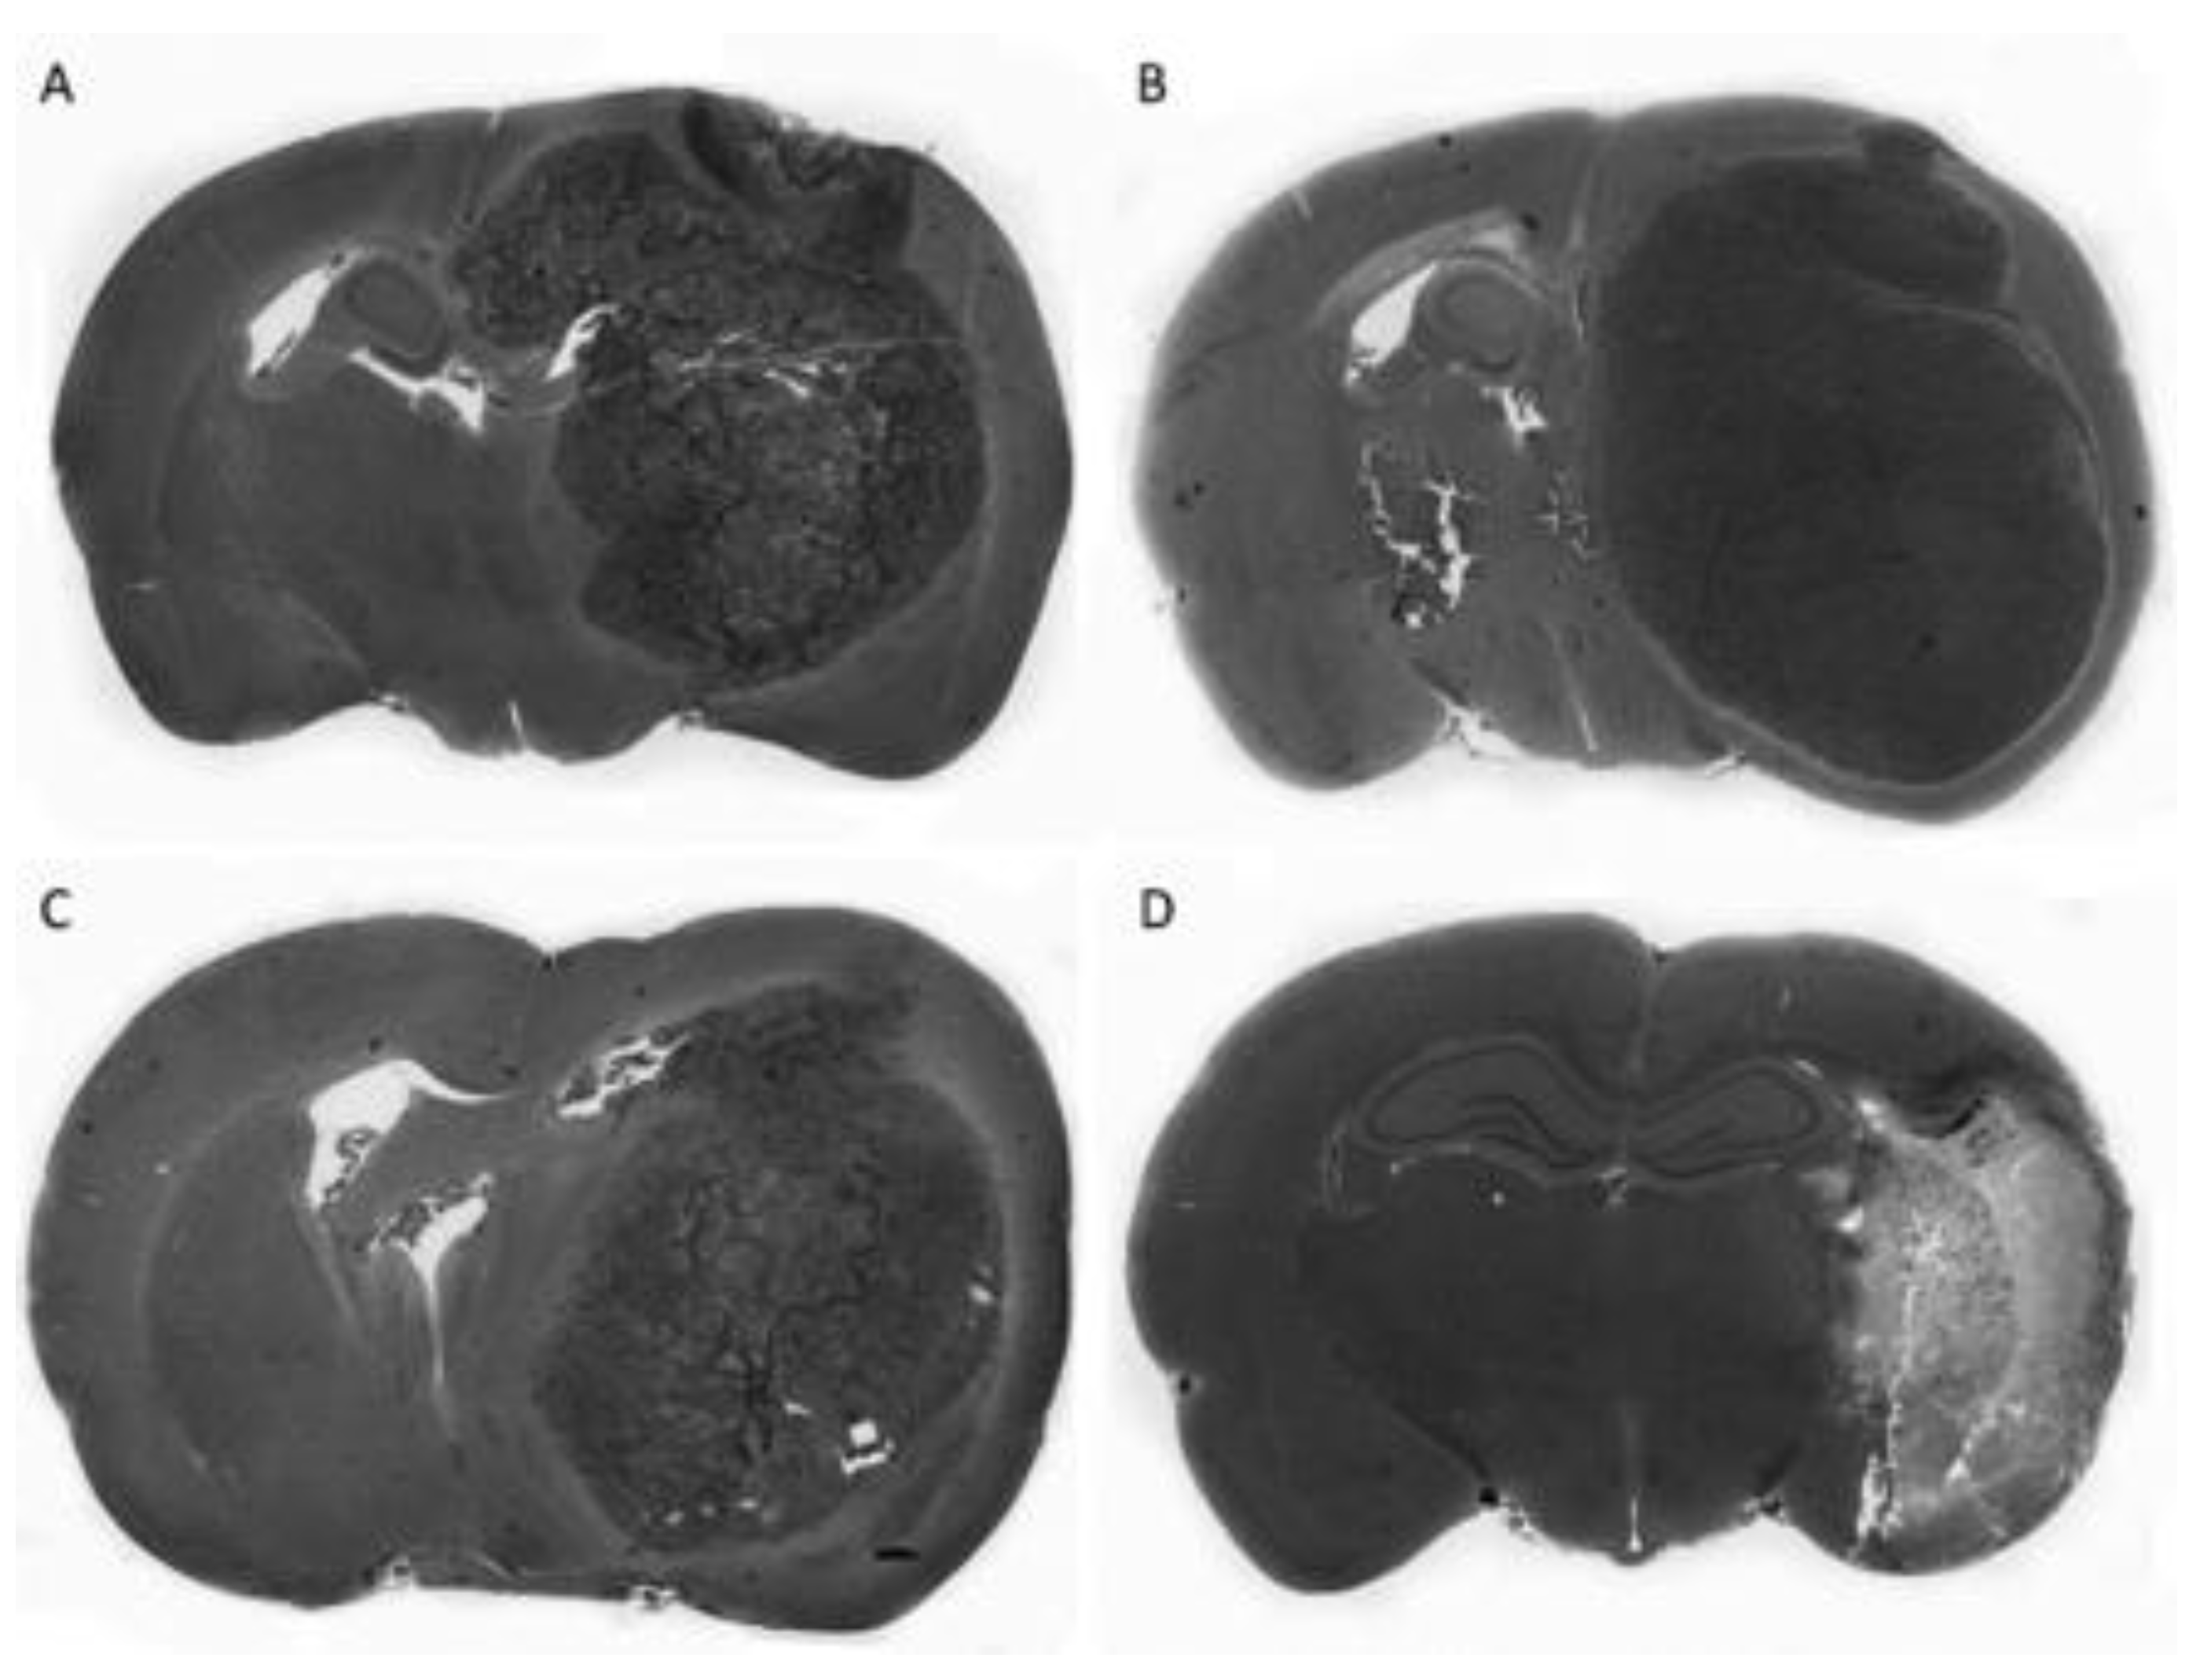

- Suehiro, S.; Ohnishi, T.; Yamashita, D.; Kohno, S.; Inoue, A.; Nishikawa, M.; Ohue, S.; Tanaka, J.; Kunieda, T. Enhancement of antitumor activity by using 5-ALA-mediated sonodynamic therapy to induce apoptosis in malignant gliomas: Significance of high-intensity focused ultrasound on 5-ALA-SDT in a mouse glioma model. J. Neurosurg. 2018, 129, 1416–1428. [Google Scholar] [CrossRef]

- Ohmura, T.; Fukushima, T.; Shibaguchi, H.; Yoshizawa, S.; Inoue, T.; Kuroki, M.; Sasaki, K.; Umemura, S. Sonodynamic therapy with 5-aminolevulinic acid and focused ultrasound for deep-seated intracranial glioma in rat. Anticancer Res. 2011, 31, 2527–2533. [Google Scholar]

- Jeong, E.J.; Seo, S.J.; Ahn, Y.J.; Choi, K.H.; Kim, K.H.; Kim, J.K. Sonodynamically induced antitumor effects of 5-aminolevulinic acid and fractionated ultrasound irradiation in an orthotopic rat glioma model. Ultrasound Med. Biol. 2012, 38, 2143–2150. [Google Scholar] [CrossRef] [PubMed]

- Wu, S.K.; Santos, M.A.; Marcus, S.L.; Hynynen, K. MR-guided Focused Ultrasound Facilitates Sonodynamic Therapy with 5-Aminolevulinic Acid in a Rat Glioma Model. Sci. Rep. 2019, 9, 10465. [Google Scholar] [CrossRef] [PubMed]